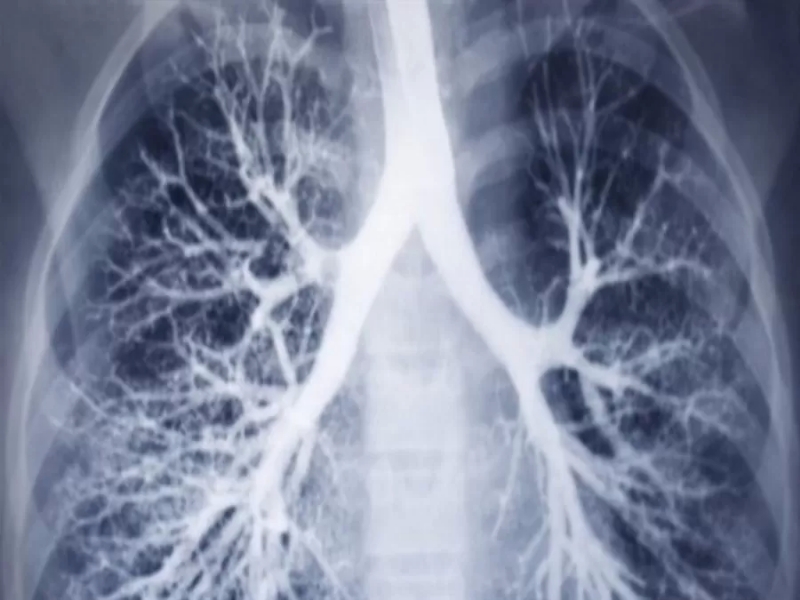

مدار الساعة -أظهرت تجارب سريرية أجريب في معهد دانا فاربر للسرطان في مدينة بوسطن الأمريكية، على مجموعة من المصابين بالسرطان بأن الجمع بين العلاج المناعي والعلاج الكيماوي يساعد على محاربة سرطان الرئة.

قلل العلاج المركب من خطر تكرار حدوث المرض أو تطوره أو الوفاة بنسبة 37 ٪ مقارنة بالمرضى الذين تلقوا العلاج الكيماوي وحده، وفقًا للنتائج التي نُشرت مؤخرًا في مجلة نيو إنجلاند الطبية.علاوة على ذلك، قتل العلاج جميع الخلايا السرطانية تمامًا لدى 24٪ من المرضى الذين تلقوه، مقارنة بـ 2٪ لدى المرضى الذين تلقوا العلاج الكيماوي فقط، كما قال الباحث في التجارب السريرية الدكتور مارك عوض، أخصائي الأورام الطبية في معهد دانا فاربر للسرطان في بوسطن.خلال الدراسة، تم استخدام علاج مناعي يدعى نيفولوماب أوبيديفو وهو علاج معتمد لمحاربة الأشكال الأكثر تقدمًا من سرطان الرئة، واختبر الباحثون ما إذا كانت إضافة عقار نيفولوماب إلى العلاج الكيماوي القياسي يمكن أن يؤدي إلى تقليص الأورام بشكل أكثر فعالية قبل الجراحة، وكذلك تقليل مخاطر عودة السرطان.وقال الباحثون إن حوالي 20٪ إلى 25٪ من المرضى الذين تم تشخيص إصابتهم بسرطان الرئة ذو الخلايا غير الصغيرة لديهم ورم يمكن إزالته جراحيًا. ولكن ما يصل إلى 55٪ من مرضى سرطان الرئة الذين أزيلت أورامهم يعانون من تكرار الإصابة بالسرطان ويموتون في النهاية بسببه.وأوضح عوض قائلاً "يمكن للجهاز المناعي التعرف على بعض أنواع السرطان على أنها لا تنتمي إلى الجسم أو أنها غريبة عن الجسم، ويحاول محاربتها. ولكن بعض السرطانات يمكن أن تتجنب أو تهرب من جهاز المناعة عن طريق صنع بروتين يسمى PD- L1، وهي إشارة على سطح الخلية السرطانية تخبر جهاز المناعة بتجاهل السرطان".وأضاف "يعمل عقار نيفولوماب عن طريق منع عملية تتجنب بها الخلايا السرطانية اكتشافها من قبل الجهاز المناعي، ويساعد على تحفيز جهاز المناعة للتعرف على السرطان ومقاومته".من جهتها قالت شركة الأدوية بريستول مايرز سكويب في بيان صحفي إنه بناءً على نتائج هذه التجربة السريرية، وافقت إدارة الغذاء والدواء الأمريكية على عقار نيفولوماب لهذا الاستخدام المحدد في المرضى الذين يعانون من أورام سرطان الرئة، وفق ما نقل موقع يو بي آي الإلكتروني.العلاج المناعي يعزز بقاء مرضى سرطان الرئة على قيد الحياة